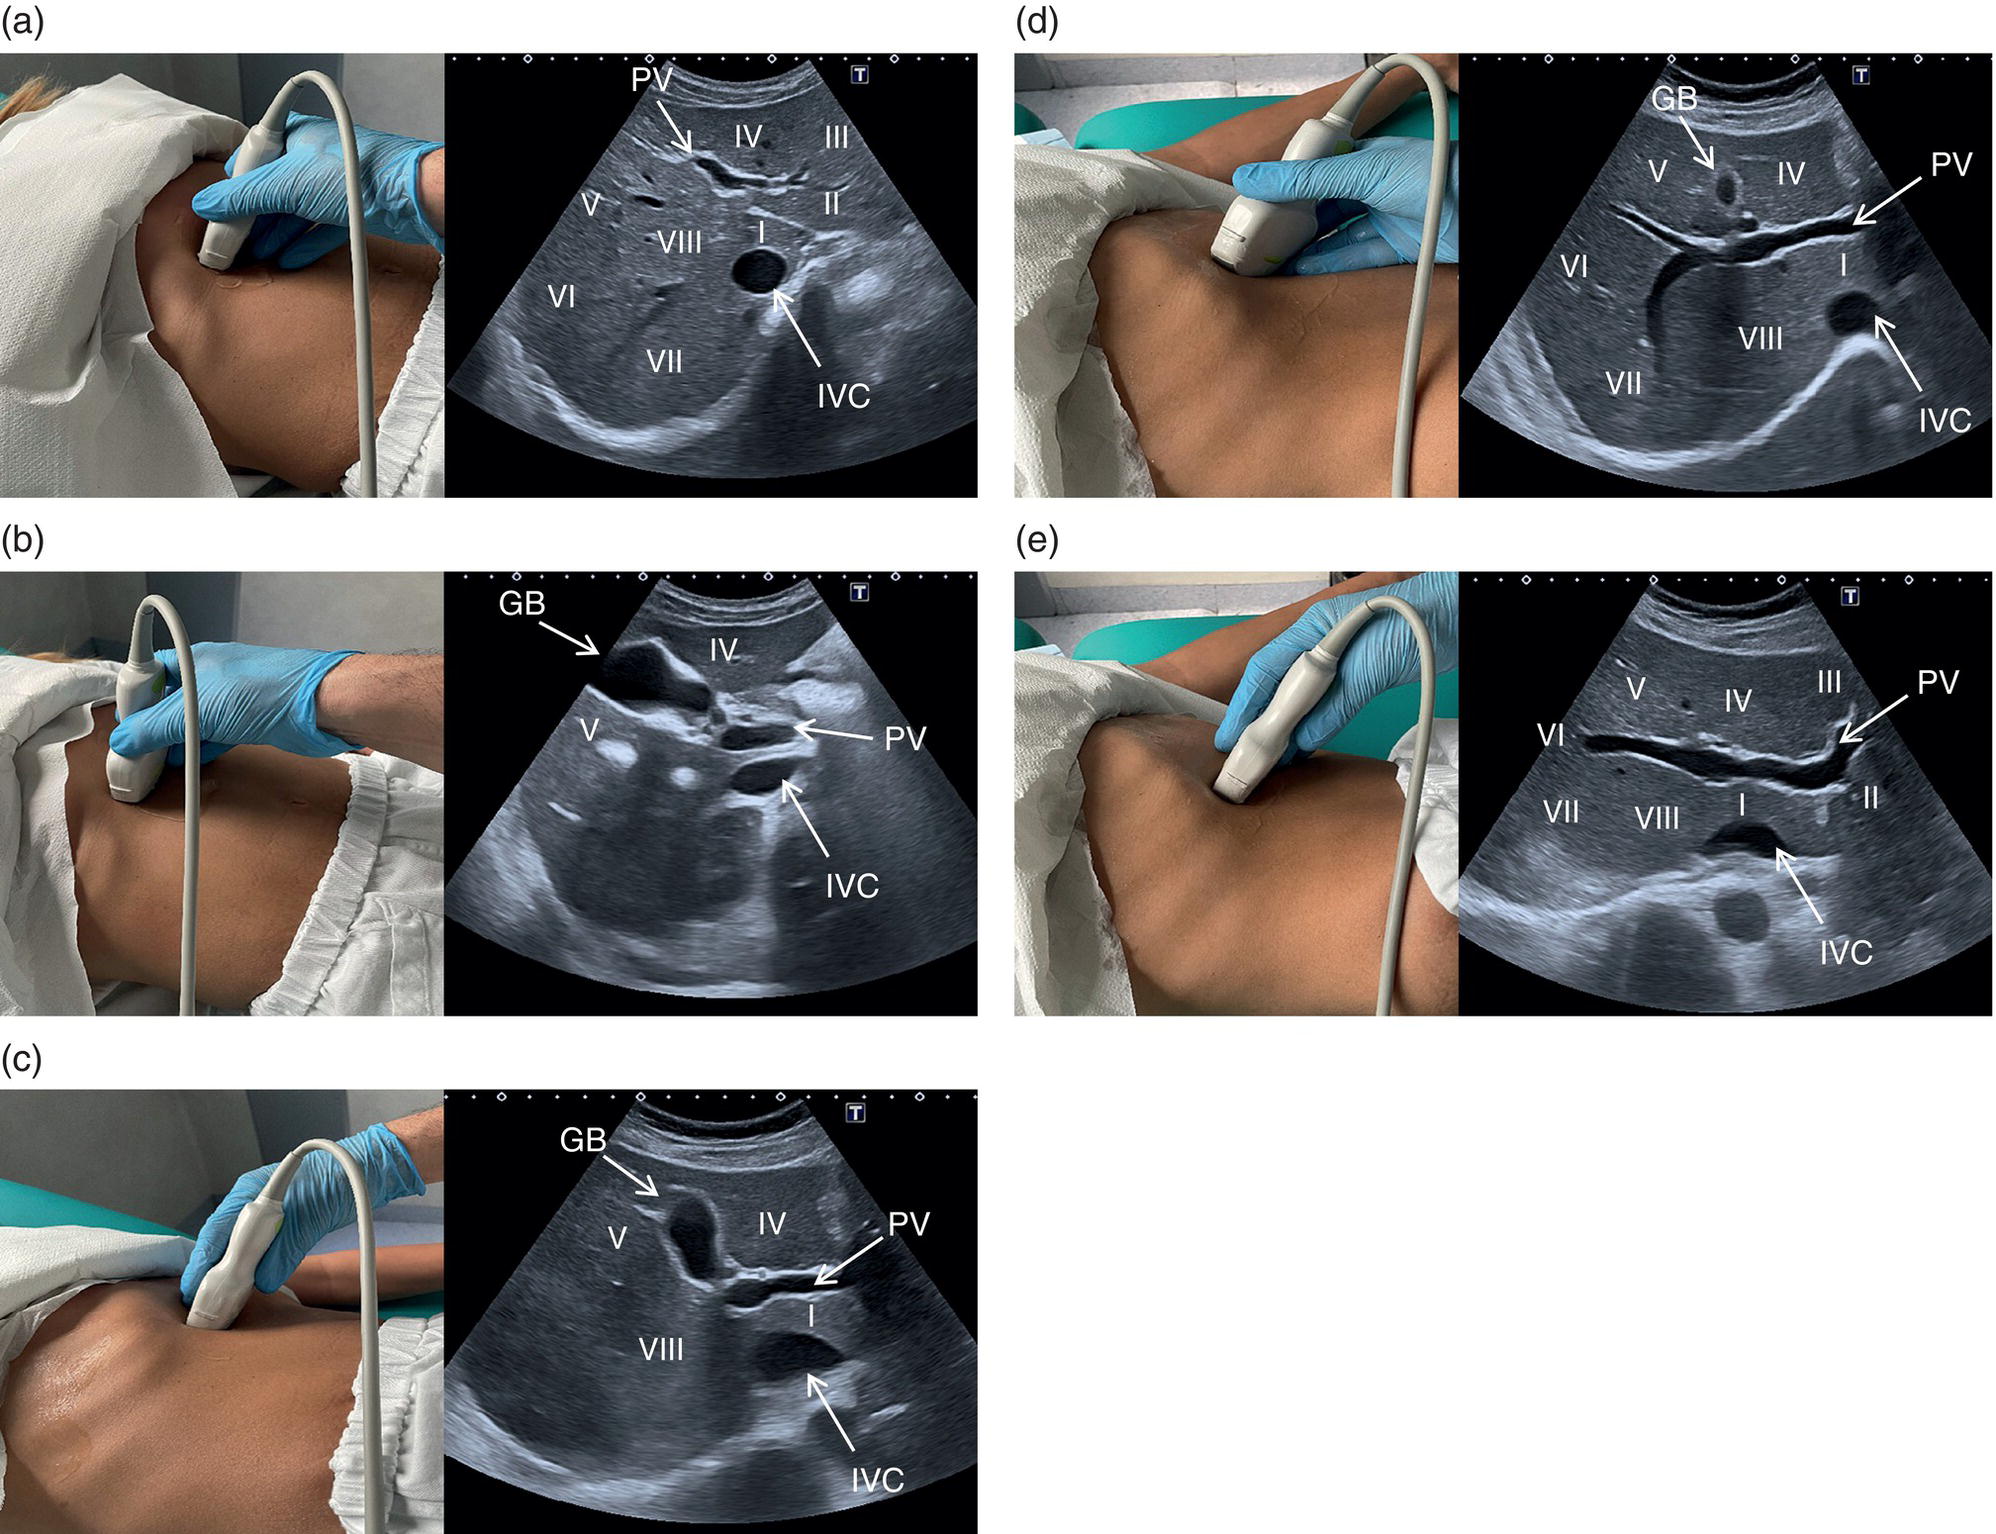

The right liver lobe includes segments V–VIII, which should be assessed in both the LS and TS planes via a subcostal and intercostal approach, as shown in Figures 3.24–3.26 (Video 3.5). Start again by keeping the probe in the epigastric region in a TS view. By angling upwards, you will visualise the most cranial liver segments (from left to right of the patient will be segment II, IV, VIII) and you will image part of the heart, eventually excluding or highlighting the presence of a pericardial effusion. Then, remaining in the subcostal scanning position, turn the probe oblique (rotating anticlockwise) and slowly angle downwards, making small adjustments as required. By doing so you will visualise the confluence of the three hepatic veins and the IVC from two slightly different angles, with the oblique scan favouring the visualisation of the right hepatic vein (Figure 3.24) (Video 3.5). Maintaining the same probe position and slowly moving downwards, you will visualise first the GB and left branch of the PV and then, eventually turning the patient left side down and making small adjustments, you will visualise the PV crossing and ‘dividing’ the liver in a cranial and caudal region (Figure 3.25) (Videos 3.6 and 3.7). Bear in mind that according to body habitus, when sweeping downwards the PV might appear before the GB or viceversa. Representative images of the right lobe should also be obtained intercostally, moving the probe from one intercostal space to another angling upwards and downwards in order to have a complete view from each angle (Video 3.5). A representative image of the liver with the right kidney is important to allow comparison of its echogenicity to the cortex of the right kidney to diagnose or exclude steatosis. This image can be obtained in the LS plane, starting along the mid‐clavicular line and sweeping outwards (laterally) until the kidney is visualised, or intercostally in case of bowel gas interference (Figure 3.26) (Video 3.8).

Based on the divisions of the portal and hepatic veins, the liver may be divided into eight segments, as first suggested by the French surgeon Claude Couinaud in 1957 (Figure 3.14) [4]. This classification relies on the fact that each of these segments has its own individual blood supply and might be resected without jeopardising the viability of other segments. In this classification, the liver segments II and III are situated to the left of the LHV and falciform ligament, and the left branch of the PV (LPV) divides them into segment II (above the PV) and segment III (below the LPV). Segment IV is situated between the LHV and the MHV and the LPV divides them into segment IVA (above the LPV) and segment IVB (below the LPV). Segments V and VIII are located between the MHV and RHV, whereas segments VI and VII represent most lateral segments situated to the right of the RHV. The right branch of the RPV divides segment V (caudal) from VIII (cranial) and segment VI (caudal) from VII (cranial) (Figure 3.15). On the dorsal, central part of the liver, between the IVC and the venous ligament, lies the caudate lobe that corresponds to segment I (Figures 3.6 and 3.12c).